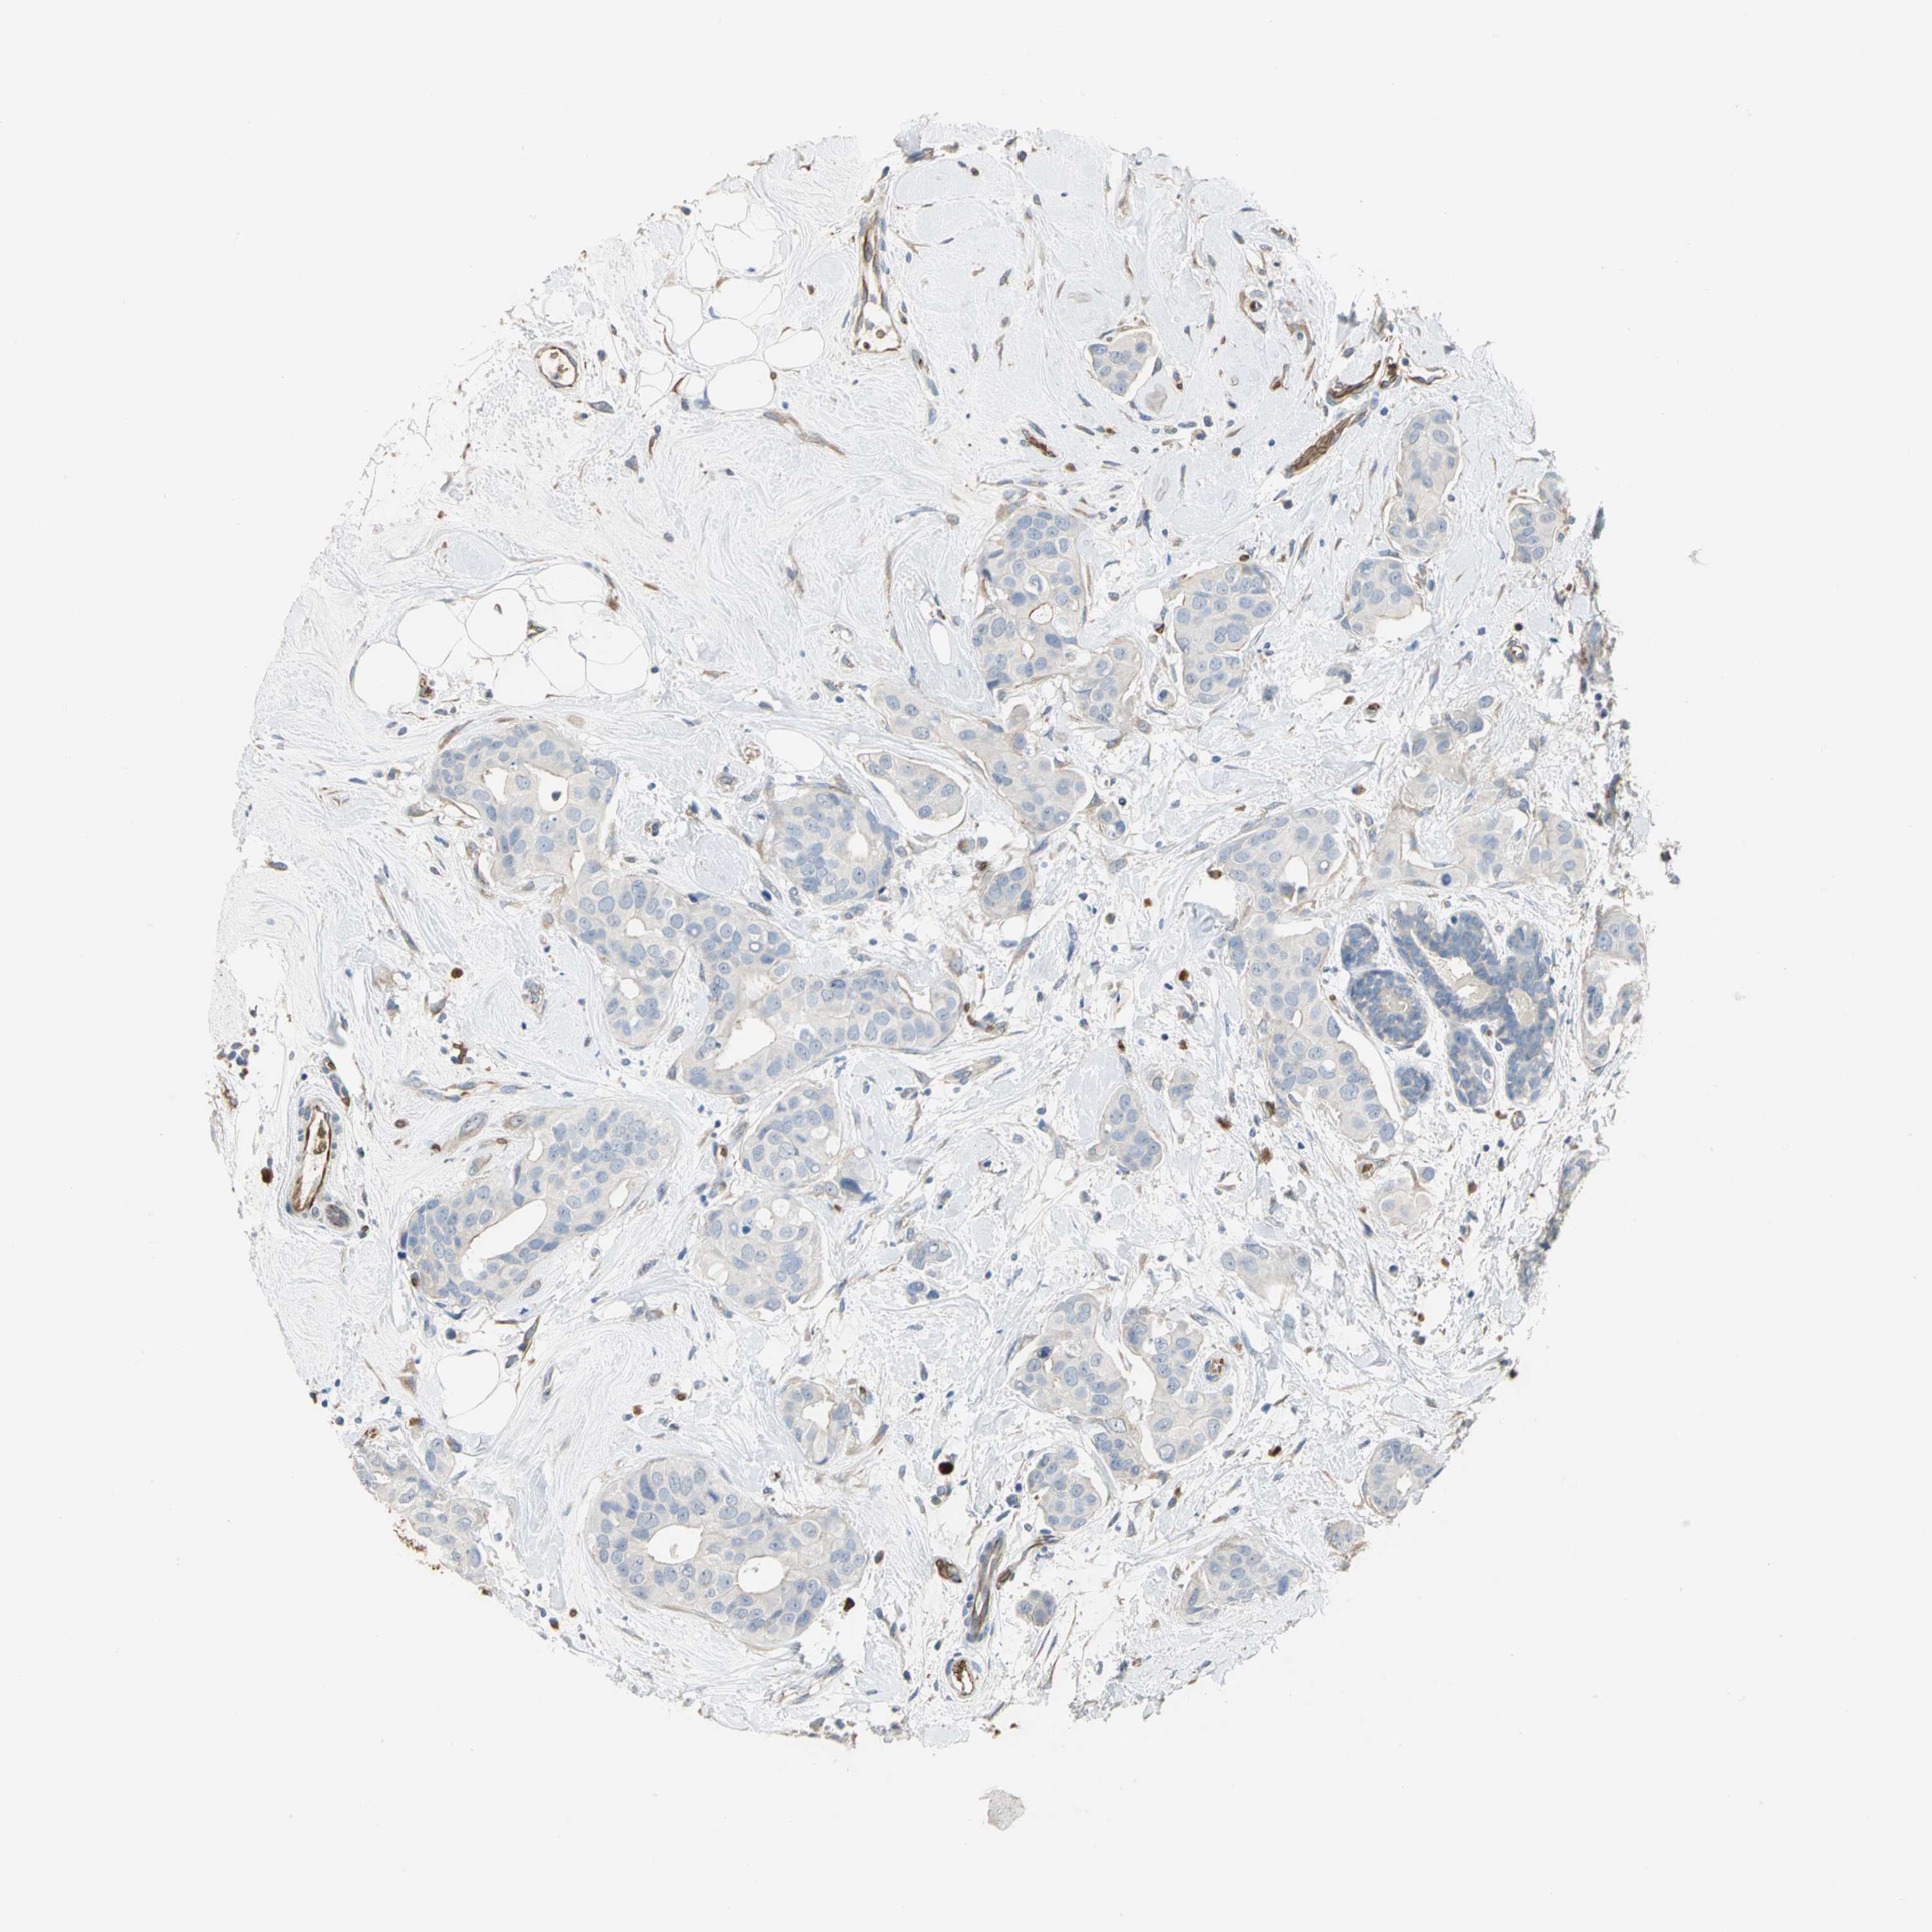

CANCER BREAST CANCER Show tissue menu

BRCA TCGA BRCA VALIDATION PROTEIN EXPRESSION

Breast cancer

Human cancer